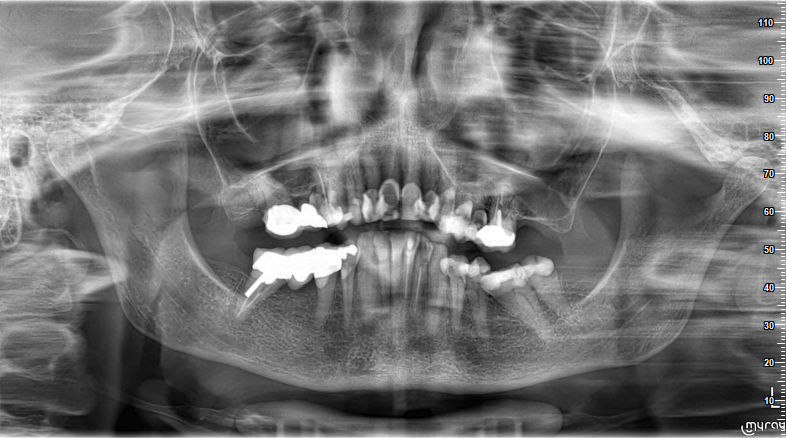

Goedemorgen, bij deze zoals beloofd een recente röntgen van mijn gebit, 2 februari 2023. Linksachter beneden heb ik af en toe kiespijn. De laatste kies is eind november 2022 opnieuw gevuld en mijn (nieuwe) nederlandse tandarts zei dat hij wel dieper had moeten boren dan hij vermoedde. Zonder verdoving gedaan en geen pijn. (V84 el.nr. 37 Meervlaksvulling glasionomeer/glascarbomeer/compomeer. Vlakken: MODB cariës naast restauratie) Nu dus pijn die komt en gaat maar wel kloppend gevoel in de onderkaak, bijna een maand. Neem soms een pijnstiller. Morgen heb ik een afspraak met mijn nieuwe Duitse tandarts die dus al een cerec brug heeft aangebracht rechtsboven achterin die hierop nog niet te zien is. Morgen zal hij achter linksboven laatste kies, een kroon vervangen maar ik denk dat ik hem beter naar die onderste kies kan laten kijken. Alhoewel hij vorige week niets raars zag: levende wortels, geen ontsteking te zien. Waar komt dat kloppen dan vandaan? Dank voor uw reactie.

De laatste kies linksonder (verstandkies) heeft geen kies ertegenover in de boven kaak ...is dus overbodig. Zonder verdoving diep geboord en geen gevoel...mogelijk een dode zenuw anders zou het mogelijk bijv. koude gevoelig zijn. Bij behoud een wortelkanaal behandeling en gezien de grootte waarschijnlijk een kroon....en dat voor een kies dat geen functie heeft...Overwegen om te verwijderen. Jammer dat de curve v kauwvlak onregelmatig is ( komt door vroegtijdige verwijdering v d eerste kies links waardoor de tweede kies gekanteld is) Zou de curve herstellen alvorens boven een kroon te maken.. Het lijkt overigens alsof daar een brug is kan op deze foto niet zien of er wortels onder de 24/25 ( eerste en tweede kleine kies) zijn.

Zou overigens zonder een herbehandeling v de laatste kies linksboven ( uw links) geen nieuw voorziening op maken. Tevens zou ik op basis v deze foto een extra foto v d 45/43/42 maken ...om uit te sluiten dat er geen ,zichtbare, ontsteking bij de wortelpunt is. Levende wortels kan je niet op een foto zien....

Het lijkt of de 6 verwijderd is en dat de laatste kies linksonder de 38 is. Bij klachten zou ik verwijderen. De kiezen ervoor liggen tegen elkaar aan dus minder kans op verder kantelen. Met koude/warmte/boren idd te testen. Maar nogmaals ik zou op basis v deze foto ( geen kanaalvulling achterste buiten wortel, "oude" WKB) geen kroon plaatsen op de 26, en rekening houden met curve herstel.

U bedoelt wkb 37.Ik zie een "zwarting" aan de MB/DB wortels v d 26. Zou daarvoor overleg plegen met een endodontoloog of een herbehandeling kans v slagen heeft eventueel een Apex resectie indien herb niet mogelijk/zinvol is. Maar zou daar zo niet een nieuw kroon plaatsen. Die ontsteking kan dus voor druk zorgen. 18 is rechts. Oorbellen altijd uitdoen bij het maken v e OPT. Ben benieuwd welke twee kanalen zijn gevonden. Deze foto is niet geschikt voor een WKB. . Om te beoordelen zou ik een duidelijk "kleine lokaal" foto willen zien liefst met de naalden in de kanalen voor de lengte foto.. Mogelijk wordt of de tweede mesiale kanaal niet gevonden zijn of gezien de inclinatie v d kies mogelijk de distale ( soms 2) kanaal. Zou oppassen voor een perforatie v d zenuwkamer bodem, wordt dun maar wederom niet met deze foto goed te beoordelen. Goed met de microscoop beoordelen.

Met deze foto is niet te zien of er caries onder zit. Als het 25 jr zo schuin is geweest hoeft dat verder geen probleem te geven. Ook hier dan een solo foto voor nodig en pocket registratie om uit te sluiten dat er een fractuur ( breuk) v d wortel is. Indien niet nodig waarom vervangen...eerst beoordelen. Op de foto mogelijk ontsteking (zwarting)dist/ bucc wortel 26 en 43. Bedoelt u de brg Rechts boven of onder. RB...is de wkb niet volgens huidige, wel v toen, standaard. Herbehandelen als dat de plek is waar u wat voelt. Dit is wel de oude foto...ouder dan wat u hiervoor geplaatst heeft.